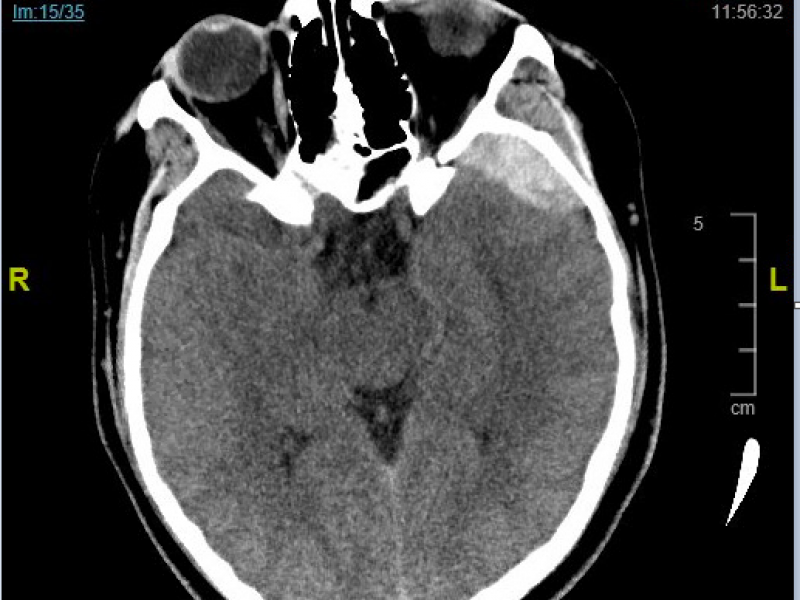

Critical Cases - Epidural Hematoma!

HPI 18 yo male restrained front seat passenger T boned by a